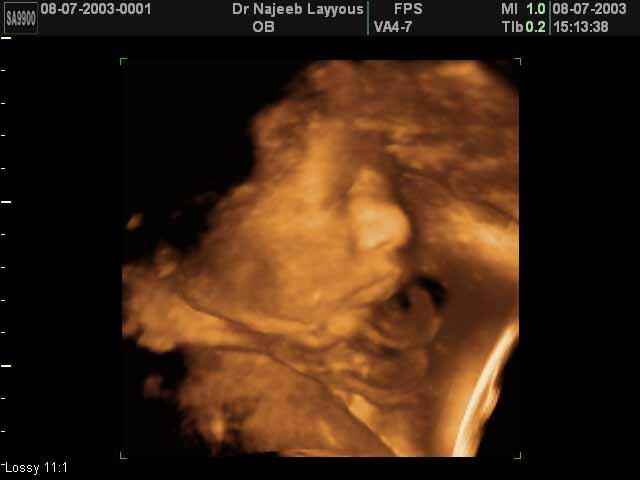

- صور جانبية لرأس الجنين

صور جانبية لرأس الجنين بجهاز الالتراساوند ثلاثي الأبعاد | الدكتور نجيب ليوس